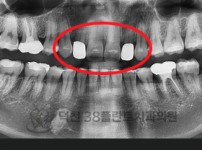

치료전후